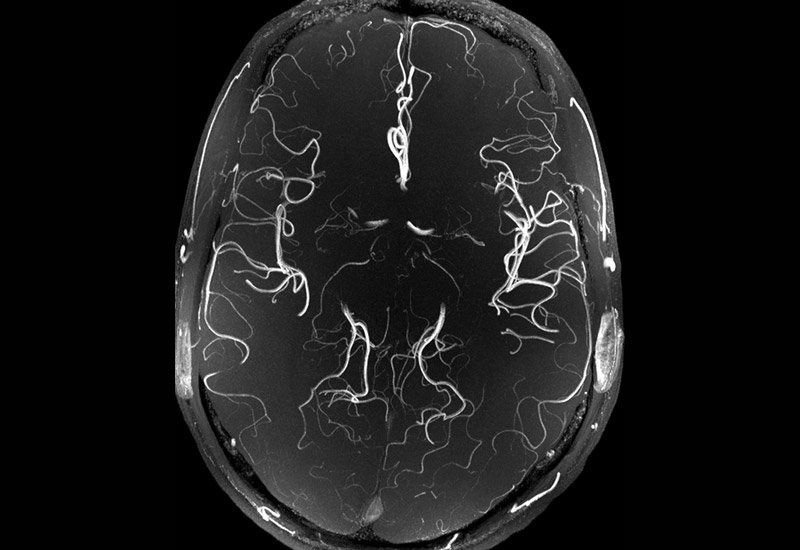

10. This magnetic resonance angiography – a type of MRI that looks at blood vessels – shows a healthy brain.